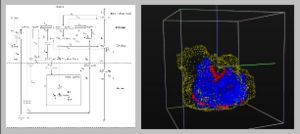

- 4.39 Using Stress MRI to Analyze the 3D Changes in Apical Ligament Geometry from Rest to Maximal Valsalva: A Pilot Study